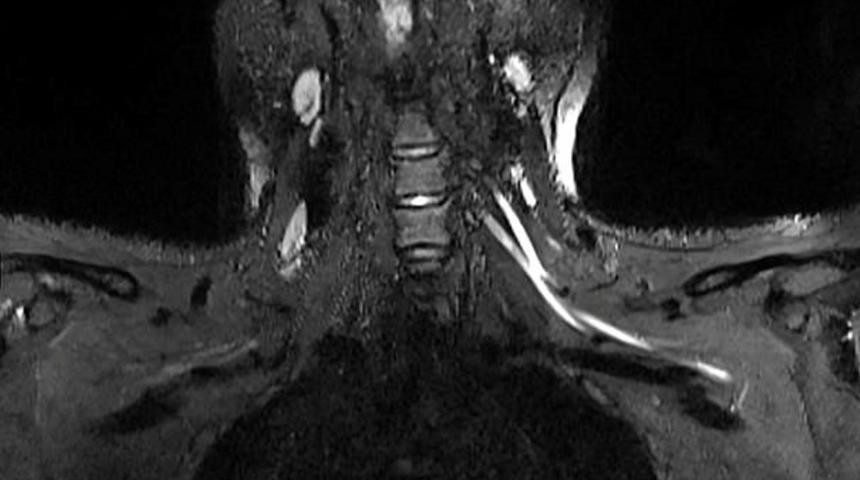

Bilim insanları yeni tip koronavirüs (Covid-19) hastalarında görülen yorgunluk ve ağrının sebebini ilk kez ortaya koydu. ABD’de yer alan Northwestern Üniversitesi’nden araştırmacılar MRI ve ultrason tekniklerini birleştirerek, geleneksel yöntemlerle tespit edilemeyen Covid-19'un sinir sisteminde yarattığı hasarı kanıtladı. Geliştirilen yeni teknolojinin doktorlara, hastaları için uygun tedavi yöntemini belirlemesini sağlayarak hayat kurtarabileceği belirtildi.

Radiology dergisinde yayımlanan çalışmanın başyazarı Doktor Swati Deshmukh, konuya ilişkin yaptığı açıklamada, “Ağrı boynunuzdaki, dirseğinizdeki veya bileğinizdeki sorunlardan kaynaklanıyor olabilir ve bunu anlamanın en iyi yolu MRI veya ultrasondur. Yaptığımız çalışmayla çok küçük sinirleri bile gösteren gelişmiş görüntüleme sunuyoruz. Bu da sorunun nerede olduğunu tespit etmemize, ciddiyetini değerlendirmemize ve buna neyin neden olabileceğini önermemize yardımcı oluyor” ifadelerini kullandı.